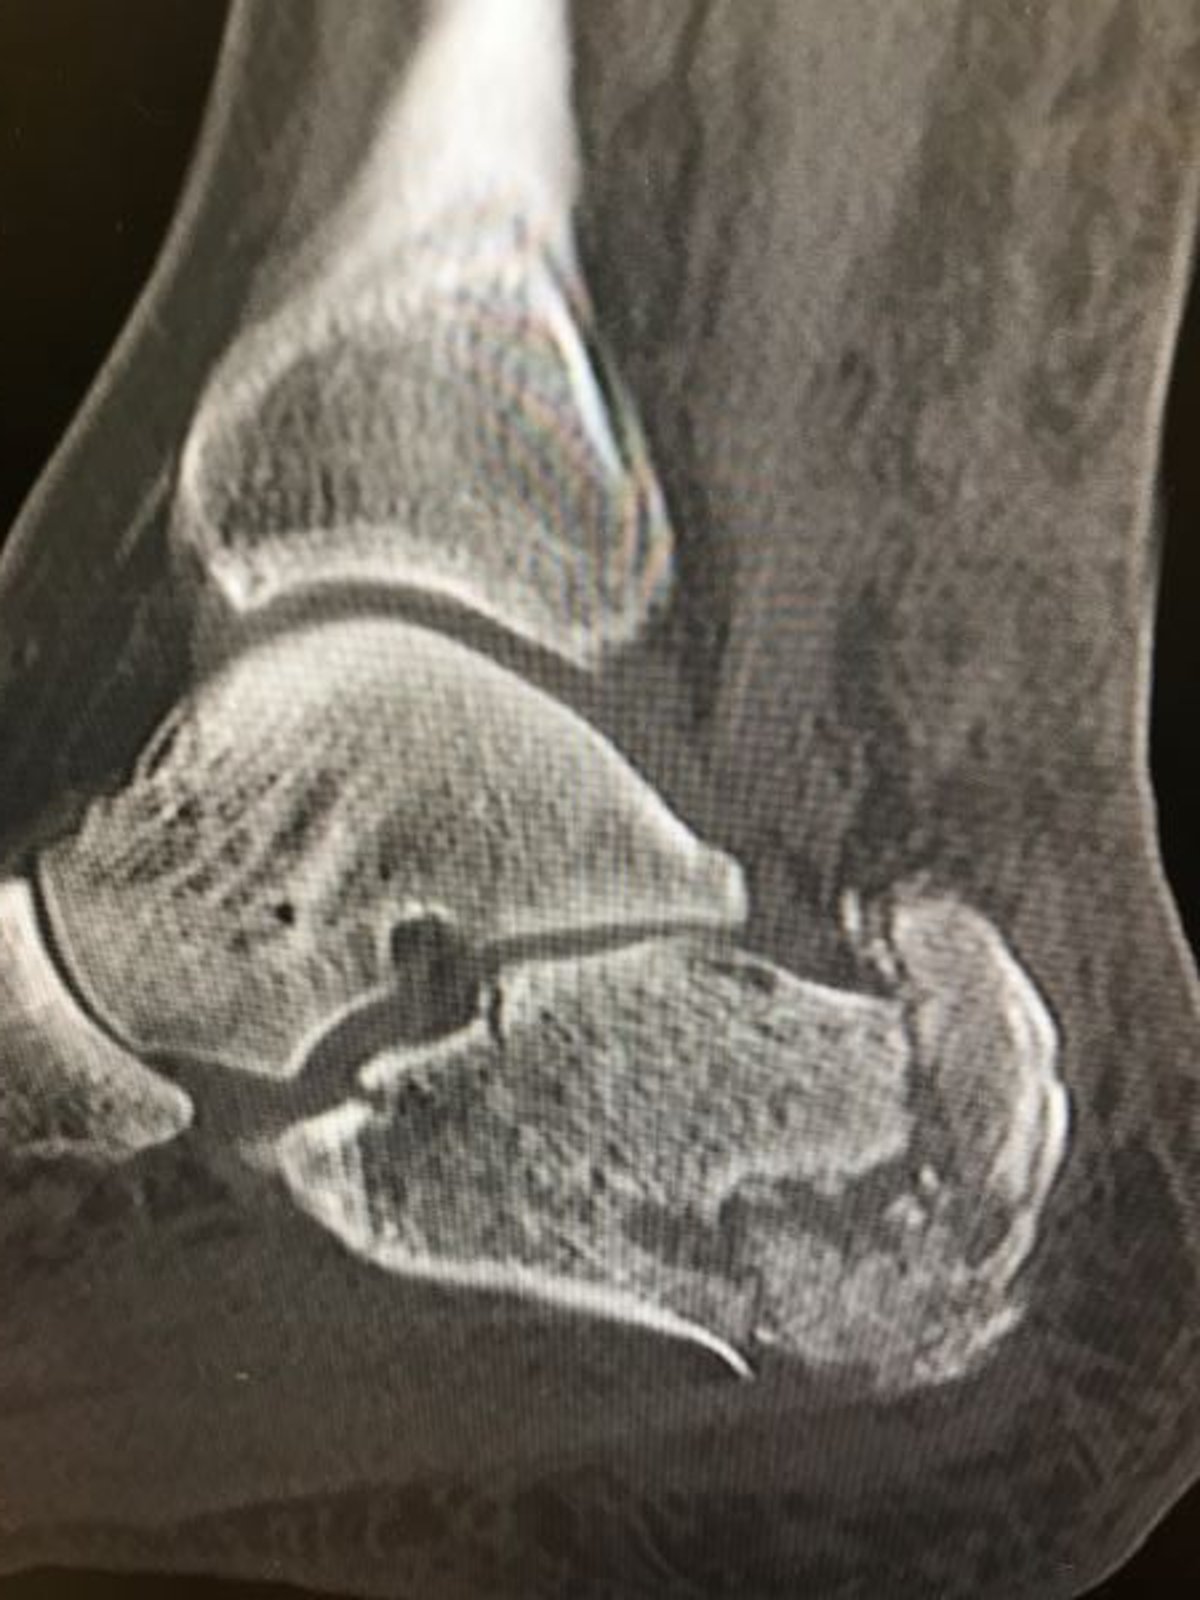

Fracture du calcanéum

Cette radiographie montre une fracture comminutive du calcanéum.

Image courtoisie de Danielle Campagne, MD.